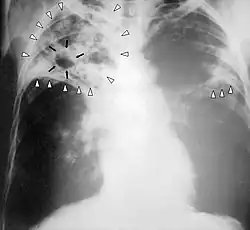

![]() Zdjęcie rentgenowskie klatki piersiowej osoby chorej na gruźlicę | |

Badanie RTG płuc

Objawy gruźlicy pierwotnej są często mało charakterystyczne, podobne do objawów grypowych. Bardziej zaawansowana postać gruźlicy daje zmiany w płucach w postaci nacieków gruźliczych, widocznych na zdjęciach radiologicznych.

Nacieki gruźlicze w prawym płucu oraz środkowym polu płuca lewego, rozpady (jamy) w górnym i środkowym polu płuca prawego, 2004

RTG klatki piersiowej u pacjenta z obustronną gruźlicą płuc